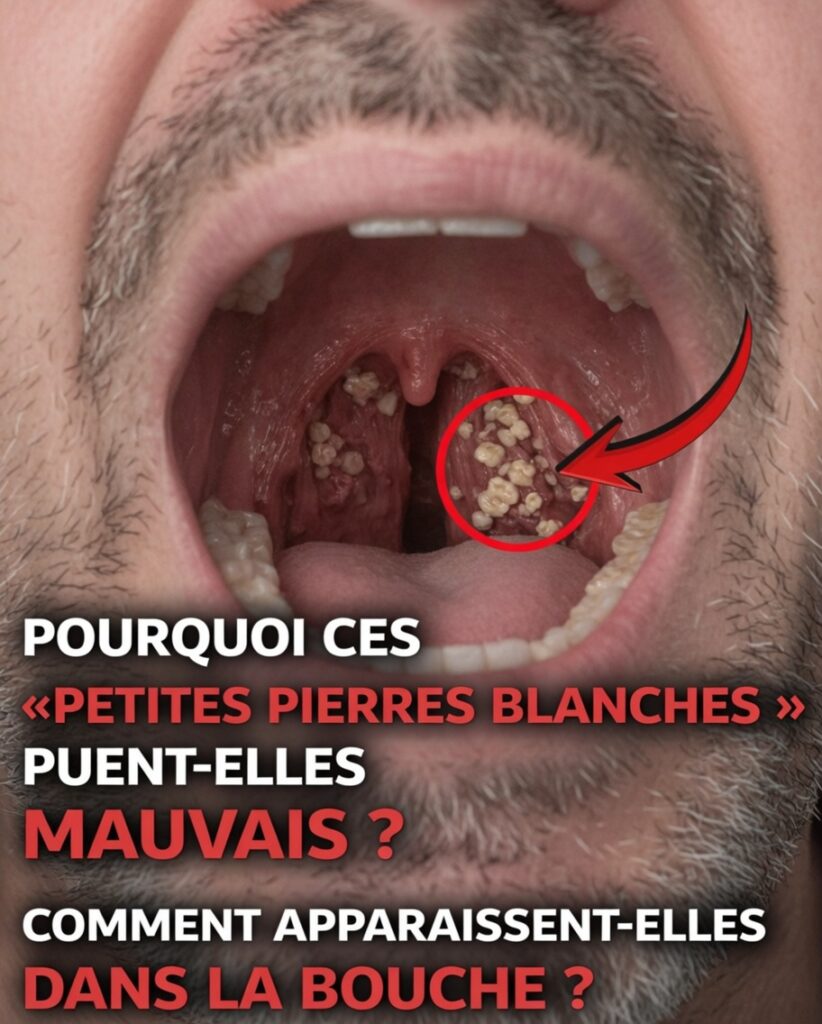

Calculs amygdaliens : ces petites masses blanches qui sentent mauvais

Les calculs amygdaliens (ces petites boules blanches, parfois expulsées en toussant) peuvent être à la fois gênants et inconfortables. Ils sont fréquents et généralement sans gravité, mais leur odeur forte peut rapidement devenir embarrassante en société. Beaucoup de personnes en ont sans le savoir… jusqu’au jour où elles les remarquent. À partir de là, mieux vaut comprendre le phénomène et agir.

Qu’est-ce qu’un calcul amygdalien ?

Les calculs amygdaliens (ou tonsillolithes) sont de petits dépôts durs, souvent blanchâtres, qui se forment dans les amygdales à l’arrière de la gorge. Les amygdales jouent un rôle dans la défense contre les infections, mais elles possèdent aussi des cryptes (petits replis et cavités) où peuvent s’accumuler :

Avec le temps, cet amas se compacte, puis se calcifie (dépôts de minéraux comme le calcium), formant un « caillou » plus ou moins visible.

La taille varie : certains ressemblent à un grain de riz, d’autres à une petite bille. Les plus petits passent inaperçus, tandis que les plus gros peuvent irriter la gorge ou être visibles au miroir.